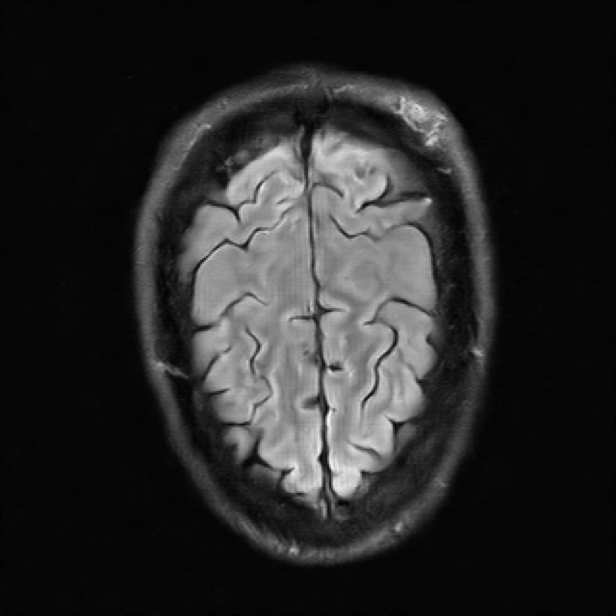

| Ground Truth | E2E-VarNet | UDNO | Nirvana (Ours) |

We also visualize the performance of Nirvana for MRI reconstruction with the undersampling rate set as 8 in Fig. 3. The ground truth, the images reconstructed by E2E-VarNet, UDNO, and Nirvana are shown in the 4 columns, respectively. As shown in Fig. 3, the performance of Nirvana is better than UDNO and E2E-VarNet in terms of the image fidelity and resolution. The reconstructed image of E2E-VarNet is blurry, and some part of the brain is completely obscured by black patches. The reconstructed image of UDNO is roughly close to the ground truth image, but the resolution is low and the details of the image are unclear. However, the reconstructed image of Nirvana is clear and accurate with high resolution, remarkably resembling the ground truth image with the highest SSIM, whose value is 0.8812.